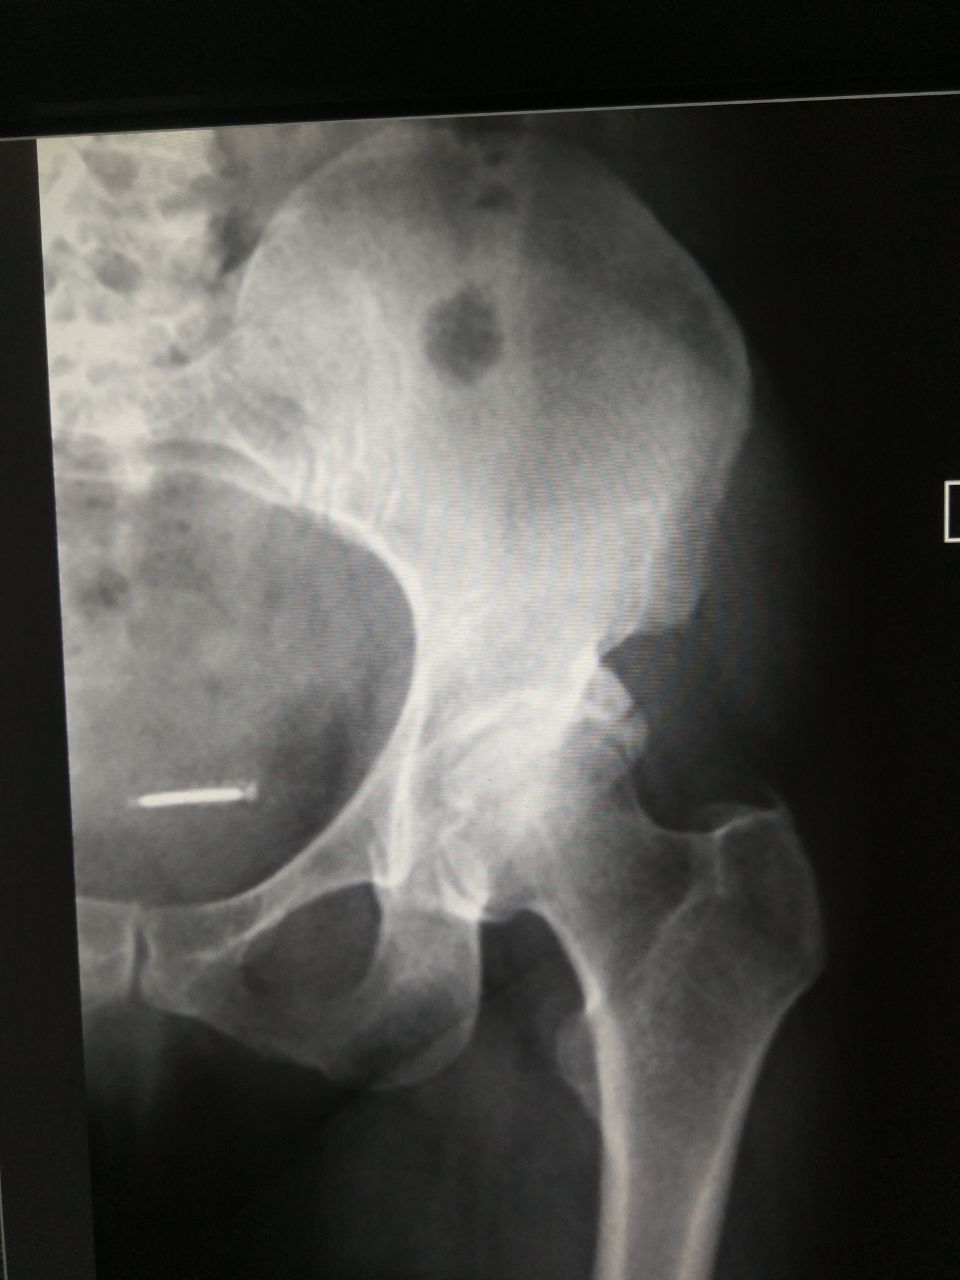

Что за тень в малом тазу? Спираль?

Как вариант, что это ещё более старая спираль